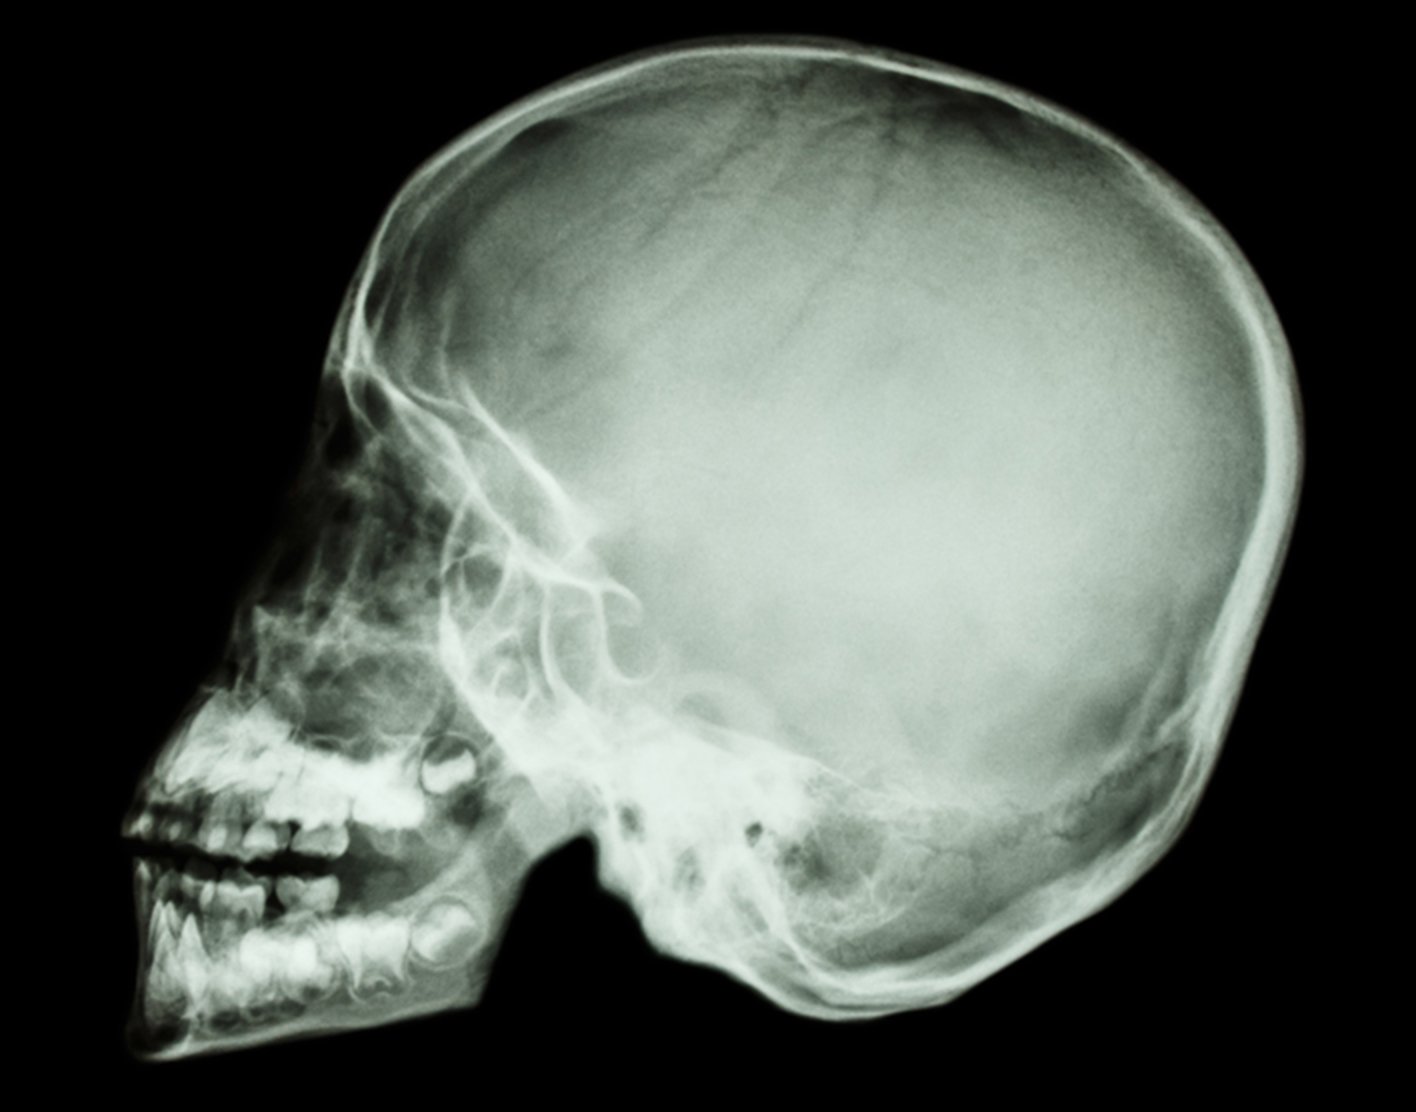

Skull x-ray

Definition

A skull